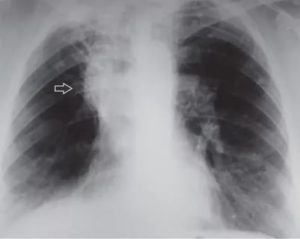

Любое остаточное явление, которое возникает вследствие деятельности палочки Коха, можно назвать метатуберкулезом. Например, очаг Гона – это метатуберкулезное изменение, возникшее после первичного туберкулеза. Локализуется он, чаще всего, в верхних долях легких. Любой очаг, локализующийся в этом месте должен вызвать подозрение на туберкулез или его остаточные явления.

- Локализация в верхних долях легких;

Как и любое патологическое изменение легочной ткани, метатуберкулез может быть локальным и диффузным. В первом случае видны один или несколько очагов, небольших по размерам, четко отграниченных от здоровой легочной ткани. Такие изменения возникают вследствие очагового или инфильтративного туберкулеза.